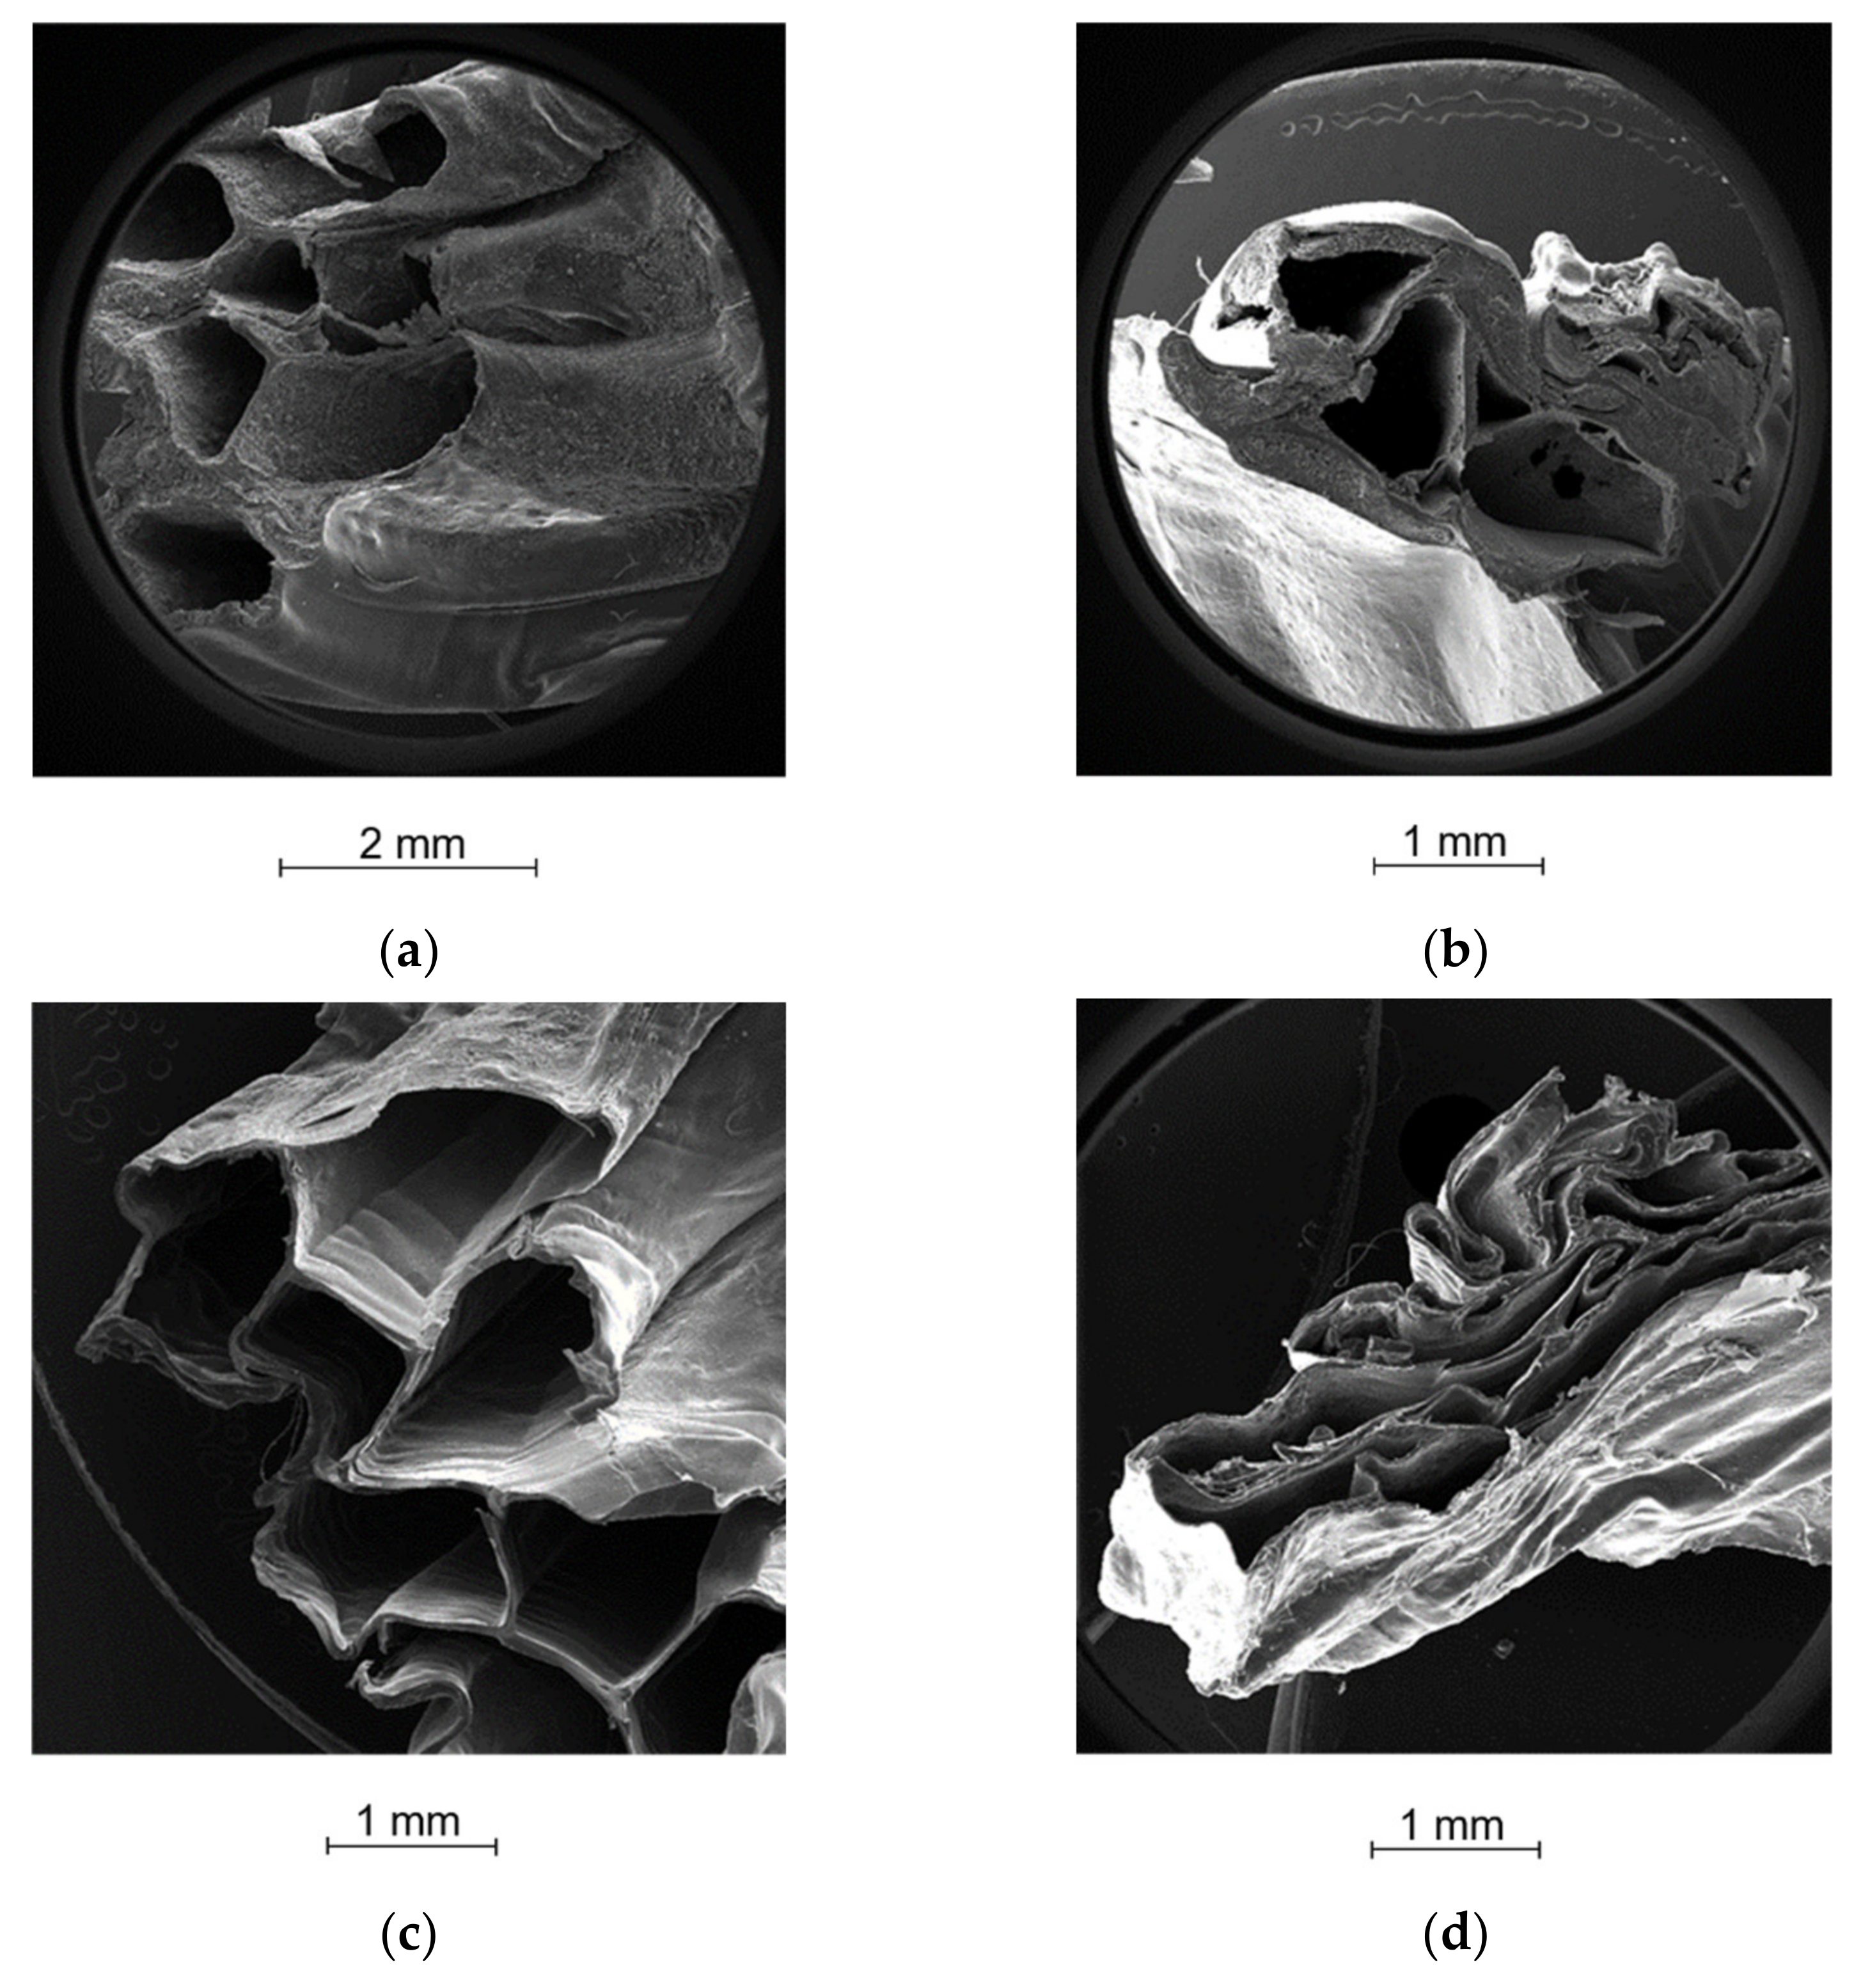

2.5. Morphological Analysis

4.2.6. Morphological Analysis